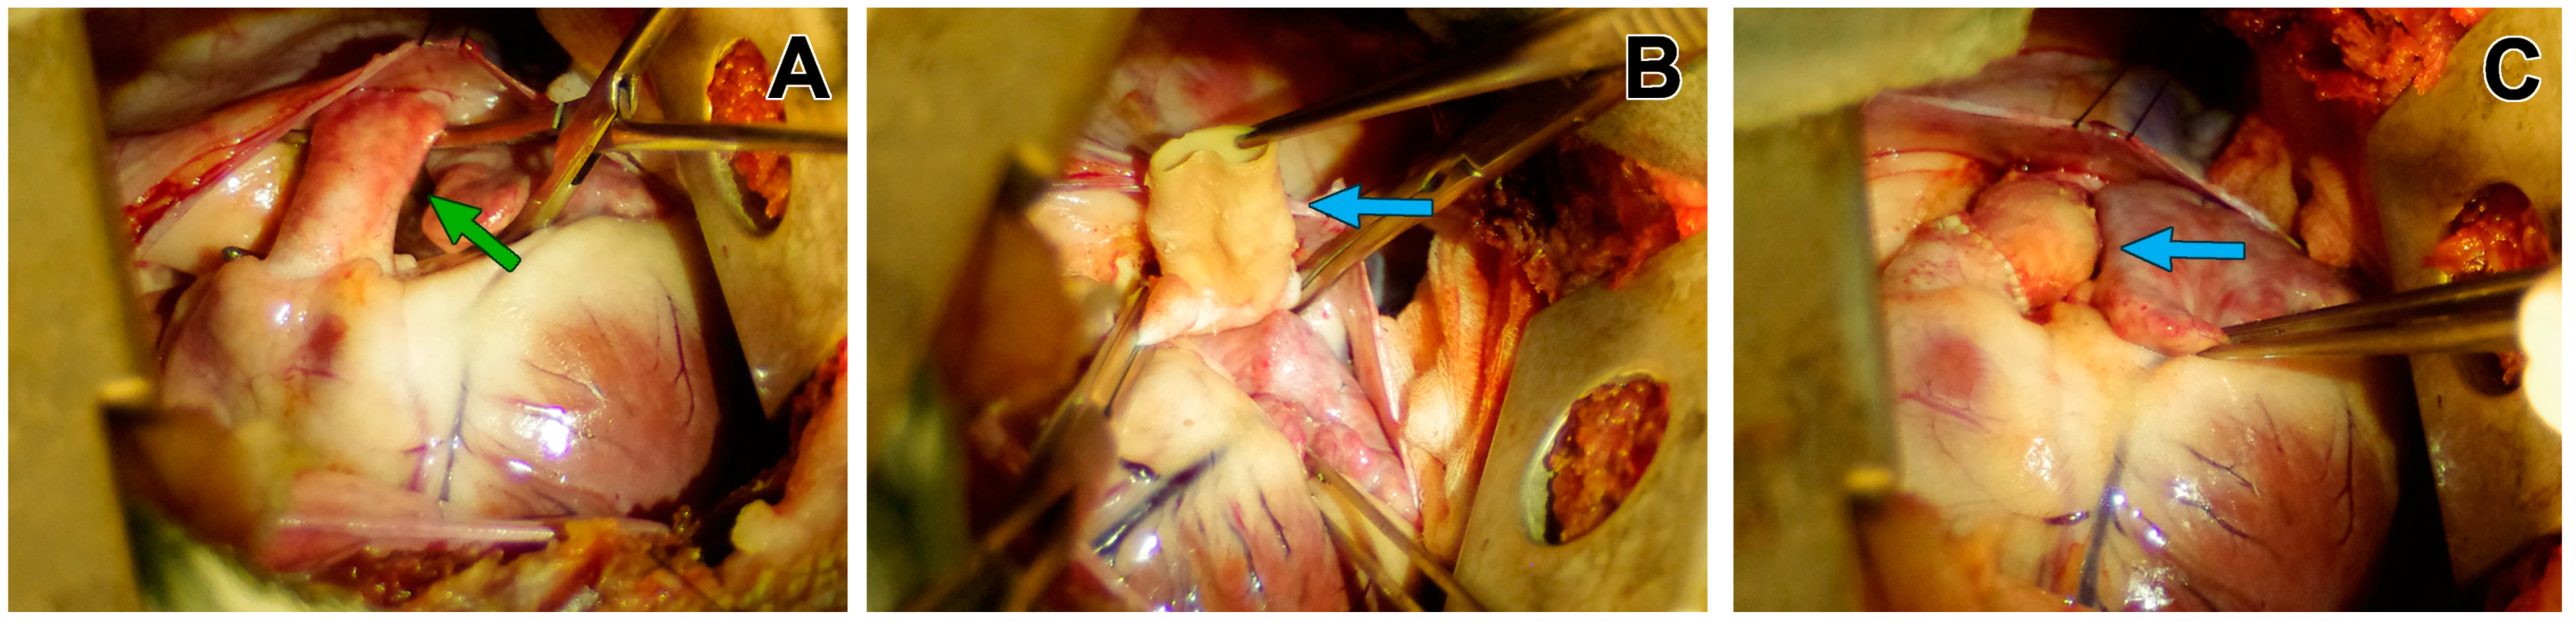

2.3.3. Operative Techniques

3.1. Macroscopic Findings